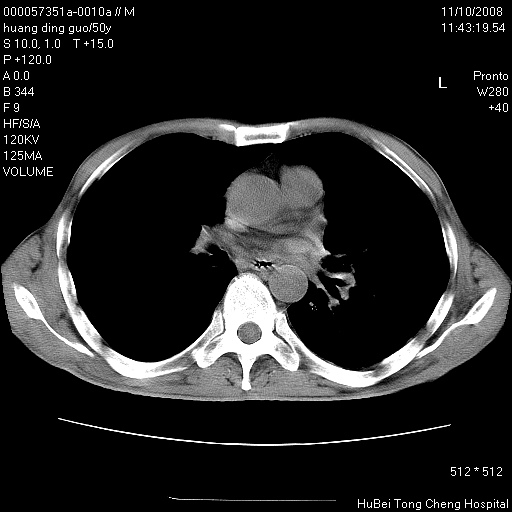

患者 男,50岁。左侧腰背部疼痛3月余,伴消瘦。平素健康,无传染病史。

胸部ct轴位平扫(层厚10mm,螺距1.5,重建间隔10mm),图像如下:

左肺下叶背段有一厚壁空洞,外壁呈锯齿状伴毛刺改变。空洞相邻胸膜有牵拉改变。左肺下叶血管支气管束不规则增粗,小叶间隔增厚。胸椎骨质破坏。考虑左肺下叶周围型肺癌伴左肺下叶癌性淋巴管炎、胸椎转移。

左肺下叶背段有一厚壁空洞,外壁呈锯齿状伴毛刺改变。空洞相邻胸膜有牵拉改变。左肺下叶血管支气管束不规则增粗,小叶间隔增厚。胸椎骨质破坏。考虑左肺下叶周围型肺癌伴阻塞性肺炎、胸椎转移。其他待排

左肺下叶背段有一厚壁空洞,内壁不规则,外壁呈锯齿状伴毛刺改变。空洞相邻胸膜有牵拉改变。周围呈絮状炎性改变,左肺下叶血管支气管束不规则增粗,小叶间隔增厚。胸椎骨质破坏。考虑左肺下叶周围型肺癌伴左肺下叶阻塞性肺炎、胸椎转移。